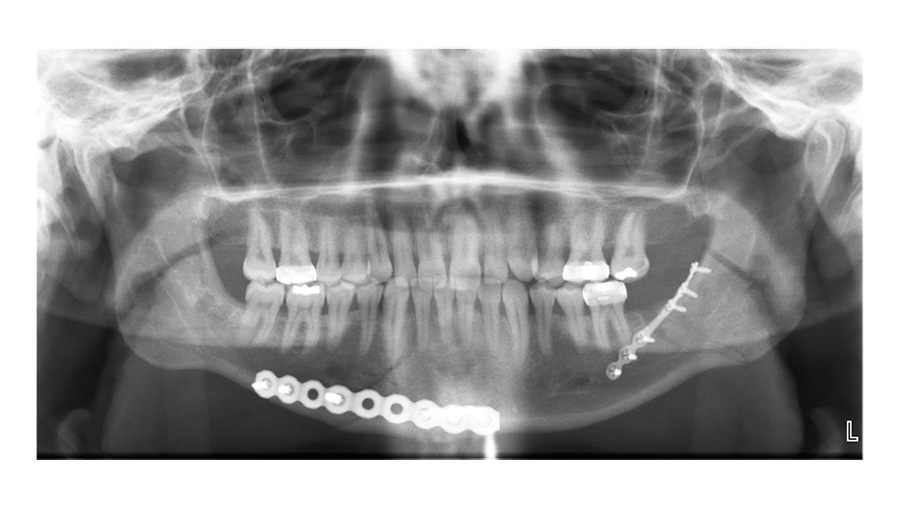

The imaging shows a right parasymphyseal fracture and a left mandibular angled fracture. And the concordance of the imaging findings with the clinical exam should be reassuring to you. Sometimes when there's a discrepancy between the two, you have to reconcile that. And one of the most important points about mandible fractures that I've learned over time and we try to stress to our own trainees is when you see a patient with what is presumed a unilateral mandible fracture, it's your job to rule out a bilateral or counter coup injury because they often occur in pairs, as you see in this case.

Now, this fracture orientation at the angle is favorable because the angulation of the fracture runs perpendicular to the masseter muscle, so you can see on the imaging that the fracture is generally nondisplaced. A subtle finding on the imaging, which is really important, is that there is a tooth in the way of the fracture which appears to be outside of the arch alignment.

Dr. Hopper: Is this an early postoperative film where you decided to take the Erich arch bars off? Or is this after healing?

Dr. Susarla: This is an early post-operative film, and in this patient, we did take the Erich arch bars off at the end of the case. We were very confident in the stability of the fixation and the patient seemed fairly reliable. So that's a decision I think that every surgeon struggles with at the end of the case like this is, are you confident enough in your fixation to not have the patient in their maxillary fixation postoperatively?

So, you have your Panorex - what are you looking for on your PA film here?

Dr. Susarla: The PA film—what I'm looking for is just the splay at the inferior border. One of the advantages of the Panorex is that it's sort of the workhorse for dentoalveolar imaging, particularly for the mandible. It shows you the condyles, it shows you the inferior border, it shows you the teeth, and it can show you the positioning of the fixation relative to the roots of the teeth.

One of the downsides of the Panorex is that it doesn't show you the transverse dimensions. If there's a little bit of lingual splaying, you might not be able to see that as well. My protocol is, particularly in young patients, if there's no compelling reason to get a postoperative CT scan, then I just get plain film imaging to verify to myself that the reduction is adequate and that the hardware looks okay.

And I'd like to get two planes of imaging, so a Panorex, and in this case, a PA ceph[alogram] to be able to show the entirety of what you would imagine three dimensionally or the information you get from a 3D CT scan just with a lower radiation dose.